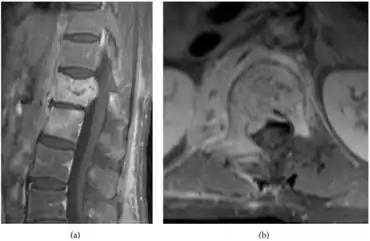

Plain-film radiological orders are necessary for all people displaying symptoms of the disease; this diagnostic approach is often preliminary to other radiological procedures, such as magnetic resonance imaging, computed tomography (CT) scan, fine-needle aspiration biopsy[5]. The initial plain-film X-ray images are scanned for any indication of disc compression between two vertebrae or the degeneration of one or more vertebrae. MRI scans do not expose the person to radiation and are highly sensitive to changes in the size and appearance of the intervertebral discs. If MRI imaging is inconclusive, the high sensitivity to erosions in the vertebrae or intervertebral discs of CT scans may be preferred for their ability to indicate signs of the disease more clearly than MRI. Additional tests may be ordered if such preliminary tests cannot confirm a diagnosis, for example, needle biopsies may be needed to take samples of bone surrounding the disc space where the infection is thought to live[13][14][5]

-

CT scan -

MRI